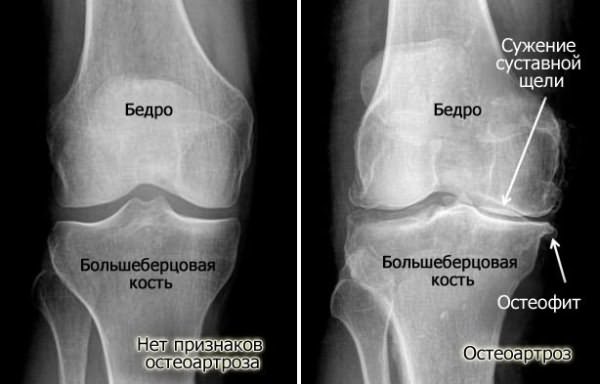

Опасность заключается в том, что на ранних стадиях заболевания симптомы могут отсутствовать. Первые проявления человек начинает ощущать только тогда, когда хрящ уже деформирован, а сустав начинает болеть и хрустеть при движении. На этом этапе можно диагностировать гонартроз, а сужение межкостной щели, видимое на рентгеновском снимке, является его характерным признаком.

- Вторая стадия сопровождается образованием костных наростов и скоплением жидкости в суставе. Боль ощущается при движении колена (или другого пораженного сустава) и усиливается во время ходьбы или даже при легкой нагрузке. Облегчение приходит только в состоянии покоя после длительного бездействия. На рентгеновских снимках видно неравномерное сужение суставной щели, хрящ почти полностью деформирован, а кости начинают соприкасаться из-за расширения в местах образования остеофитов.

- Гонартроз третьей степени проявляется почти постоянной сильной болью, даже в покое, и постоянным поиском удобной позы для облегчения состояния. На рентгене суставная щель практически не видна, а деформация костей выражена.

При подаче жалобы на дискомфорт в суставах наиболее распространенной диагностической процедурой является рентгенография. Этот метод позволяет оценить состояние сустава и определить необходимость дальнейшего лечения. Если рентген не предоставляет полной информации (например, из-за неудачного положения, что часто наблюдается с тазобедренным суставом), может быть назначено МРТ пораженной области.

По результатам снимка можно определить размеры суставной щели относительно нормы. Существует прямая зависимость: чем больше отклонение, тем более запущена болезнь.